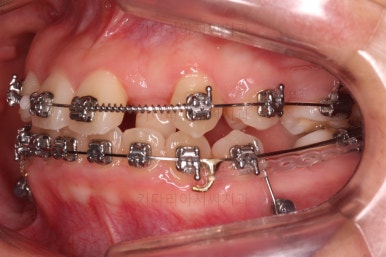

이원교정을 하신지 총 30개월 만에 남아있던 유치 자리가 잘 다물어졌고요.

이 뽑은 자리도 잘 메워졌고, 앞니도 가지런해졌어요.

위아래 치아 갯수도 동일하게 교합도 잘 맞췄고요.

예상보다 빠른 기간 안에 매우 만족스러운 치료였어요.

미니스크류가 등장했네요.

아랫니는 아무 생각 없이 당기기 해주면 앞니가 너무 들어가 입이 합죽해질 수 있으니 앞니가 들어가는 양을 조절하기 위해서 미니스크류를 사용해주어요.

적절한 시기부터는 어금니만 100% 앞으로 당겨와야 했기 때문이죠.